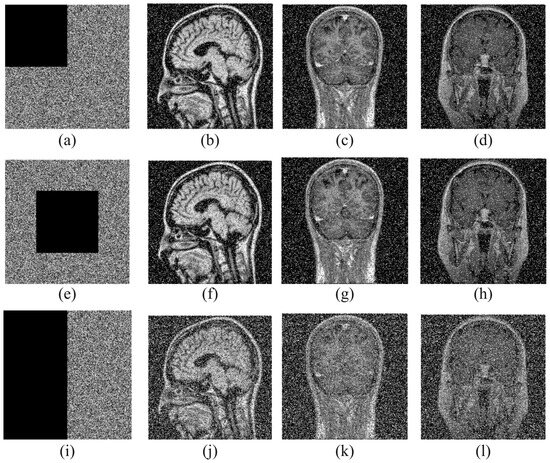

4.8. Noise Attacks

Various forms of noise in the communication channel often affect encrypted images. A good encryption system should be able to successfully recover the source image from the noisy encrypted image. In our work, salt-and-pepper noises of different intensities are added to the encrypted image to measure the robustness against noise. Decryption was then performed. The results are shown in Figure 8. Table 9 shows the PSNR values obtained as a result of salt-and-pepper noise attacks.

Figure 8.

Decryption images under salt-and-pepper noises of different intensities: (a–c) intensity is 0.01, (d–f) intensity is 0.05, (g–i) intensity is 0.1.

Table 9.

PSNR value of images obtained as a result of salt-and-pepper noises.

According to the obtained results, it is clear that the source image can be successfully restored even if the encrypted images are subjected to noise. Therefore, it is seen that the proposed method is robust against noise attacks.